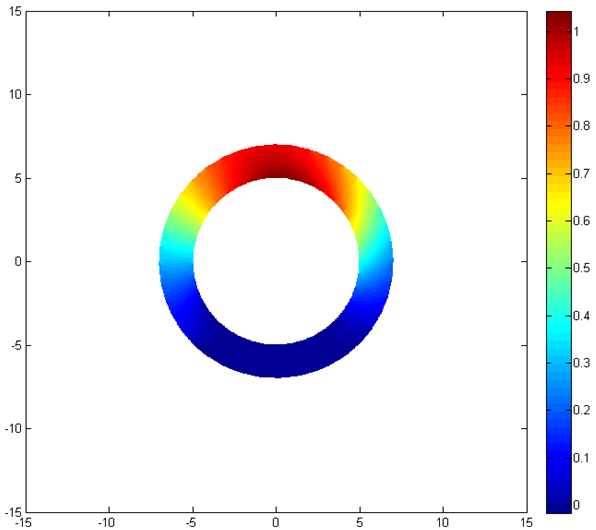

After the analysis with ANSYS, the proposed model should be implemented and the results should be compared and verified with the results of ANSYS analysis. At first the inner and our contours of the ring is determined. Then, after setting the boundary conditions, the governing equation of deformation is solved using FEM and the deformation maps are created. All the code is implemented in MATLAB.

Fig. 4 represent the results of the proposed method for both horizontal, vertical and absolute displacement. To better be able to compare the results, the ring is divided into 16 sub-regions and the results of ANSYS and MATLAB implementations are compared. Fig. 5 shows the average displacement in each region for 10 iterations of pressure increment for both ANSYS and proposed method. Based on the provided results, it can be seen that the proposed model is consistent with the results of ANSYS, even in regions with low mobility (regions 11, 12, 13 and 14).